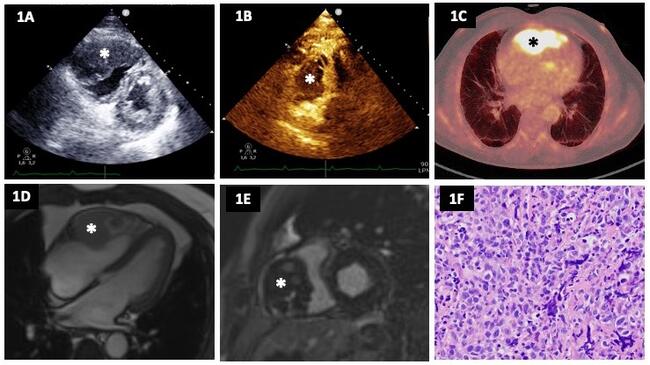

A 69-year-old man who underwent a liver transplant in 2014 due to hepatitis C virus hepatopathy was evaluated for dyspnea on exertion and chest pain. A stress echocardiogram was requested, revealing a heterogeneous mass with poorly defined borders infiltrating the right ventricle (RV) (Figure A). Due to suspicion of malignancy, the study was complemented with an echocardiographic contrast agent, which showed a heterogeneous uptake of the mass that confirmed its vascularization (Figure B; Video). The patient was admitted to the hospital for further study.

In the computed tomography (CT) body scan, no evidence of another primary tumor or distant metastasis was found. The positron emission tomography (PET)-CT showed pathological uptake at the heart (maximum standardized update value: 18.08) (Figure C).

Magnetic resonance imaging was also performed, which confirmed that the tumor infiltrated the anterior and lateral walls of the RV, had heterogeneous contours, and measured 6 x 4 x 7 cm (Figure D and E). The mass caused partial occlusion of the RV cavity without affecting the atrioventricular groove or the right coronary ostium. It showed intermediate intensity in the T2 and short-tau inversion recovery sequences, heterogeneous perfusion in perfusion sequences, and diffuse uptake in late gadolinium enhancement.

Finally, the endomyocardial biopsy allowed us to obtain a definitive diagnosis of post-transplant diffuse germinal center B-lymphoproliferative tumor located in the heart (Figure F). The patient is currently being treated with chemotherapy with a positive response, as confirmed by the follow-up PET-CT.